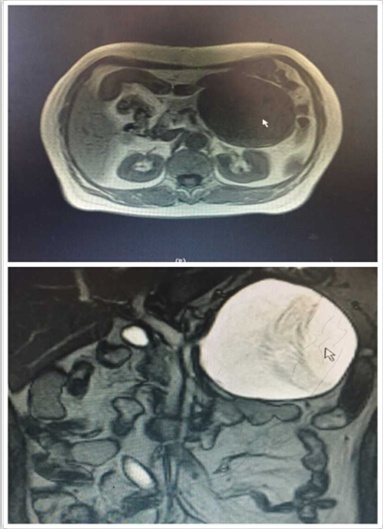

近日,我院肝膽外科入住一位65歲老年女性患者。該患者是一位退休工人,平日生活樸素,一年前自覺有上腹部隱痛不適,每次腹痛發(fā)作便自行于藥店買藥“治療”。可是近段時(shí)間,該患者感覺腹痛進(jìn)行性加重,腹部出現(xiàn)隆起,進(jìn)食少量食物便會(huì)出現(xiàn)腹脹、惡心、嘔吐不適,遂來我院就診。門診行腹部CT檢查發(fā)現(xiàn)胰腺巨大占位性病變(圖1),此時(shí)患者才恍然大悟,立即入住肝膽外科進(jìn)行治療。

圖1